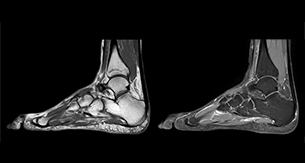

“In peripheral joints, mDIXON TSE imaging aids in diagnosing injuries in ligaments or tendons, for imaging degenerative and inflammatory pathologies such as osteoarthritis and rheumatologic disorders and for oncological exploration.” “For tendon and ligament assessment around knee, ankle, hip and elbow, mDIXON TSE contributes to diagnostic confidence thanks to having images both with and without fat suppression – and without time penalty. This is possible because 2-point mDIXON is faster than the common 3-point Dixon method. It can also increase efficiency as it helps avoid having to add scans during the exam.” “mDIXON TSE sequences allow simultaneous characterization of morphological changes from the in-phase T2-weighted images and visualization of edematous changes, thanks to the water T2-weighted images from the same acquisition. Anatomical and morphological considerations could be a partial or complete ligament tear, a bony avulsion or hematoma.” “For soft tissue assessment mDIXON brings similar benefits. For example in one T2-weighted mDIXON TSE acquisition, having the multiple contrasts helps us assess abnormalities in peripheral nerves fascicles, which may be due to anatomical or inflammatory changes..” “In peripheral joints, we get good image quality in difficult areas with mDIXON TSE. Fat suppressed images appear homogeneous over the entire image, even with large coverage at 3.0T – for instance in scapular or hip girdles – or in the bearing areas or around metal prostheses*, where fat suppression is often deficient with STIR or spectral fat suppression, causing diagnostic difficulties. If a diagnostic image is right the first time, we don’t need to repeat or add a sequence.” “mDIXON TSE sequences allow simultaneous characterization of morphological changes from the in-phase T2-weighted images and visualization of edematous changes, thanks to the water T2-weighted images from the same acquisition. Anatomical and morphological considerations could be a partial or complete ligament tear, a bony avulsion or hematoma.” “For soft tissue assessment mDIXON brings similar benefits. For example in one T2-weighted mDIXON TSE acquisition, having the multiple contrasts helps us assess abnormalities in peripheral nerves fascicles, which may be due to anatomical or inflammatory changes..”

“In peripheral joints, we get good image quality in difficult areas with mDIXON TSE.

Fat suppressed images appear homogeneous over the entire image, even with large coverage at 3.0T – for instance in scapular or hip girdles – or in the bearing areas or around metal prostheses, where fat suppression is often deficient with STIR or spectral fat suppression, causing diagnostic difficulties. If a diagnostic image is right the first time, we don’t need to repeat or add a sequence.” “mDIXON TSE sequences allow simultaneous characterization of morphological changes from the in-phase T2-weighted images and visualization of edematous changes, thanks to the water T2-weighted images from the same acquisition. Anatomical and morphological considerations could be a partial or complete ligament tear, a bony avulsion or hematoma.” “For soft tissue assessment mDIXON brings similar benefits. For example in one T2-weighted mDIXON TSE acquisition, having the multiple contrasts helps us assess abnormalities in peripheral nerves fascicles, which may be due to anatomical or inflammatory changes..” “mDIXON TSE sequences allow simultaneous characterization of morphological changes from the in-phase T2-weighted images and visualization of edematous changes, thanks to the water T2-weighted images from the same acquisition. Anatomical and morphological considerations could be a partial or complete ligament tear, a bony avulsion or hematoma.” “For soft tissue assessment mDIXON brings similar benefits. For example in one T2-weighted mDIXON TSE acquisition, having the multiple contrasts helps us assess abnormalities in peripheral nerves fascicles, which may be due to anatomical or inflammatory changes..” “In peripheral joints, we get good image quality in difficult areas with mDIXON TSE. Fat suppressed images appear homogeneous over the entire image, even with large coverage at 3.0T – for instance in scapular or hip girdles – or in the bearing areas or around metal prostheses*, where fat suppression is often deficient with STIR or spectral fat suppression, causing diagnostic difficulties. If a diagnostic image is right the first time, we don’t need to repeat or add a sequence.” “mDIXON TSE sequences allow simultaneous characterization of morphological changes from the in-phase T2-weighted images and visualization of edematous changes, thanks to the water T2-weighted images from the same acquisition. Anatomical and morphological considerations could be a partial or complete ligament tear, a bony avulsion or hematoma.” “For soft tissue assessment mDIXON brings similar benefits. For example in one T2-weighted mDIXON TSE acquisition, having the multiple contrasts helps us assess abnormalities in peripheral nerves fascicles, which may be due to anatomical or inflammatory changes..”